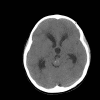

The patient was a 5 year-old Vietnamese boy who presented with the chief complaints of headaches, vomiting, and ataxia.  CT scan revealed a pineal tumor with small calcifications and hydrocephalus (Panel 1).  On MRI, the mass is a well demarcated midline mass involving the pineal area. There is also heterogeneous enhancement and cystic component (Panel 2 and 3).